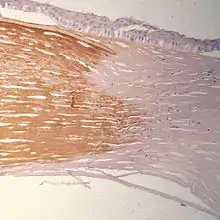

Ряд протеогликанов семейства SLRP (small leucine-rich proteoglycan) объединены под названием «кератансульфатные протеогликаны» (англ. keratan sulfate proteoglycans, KSPG); эти белки, в особенности кератокан, люмикан, мимекан (остеоглицин), играют важную роль в поддержании прозрачности роговицы.